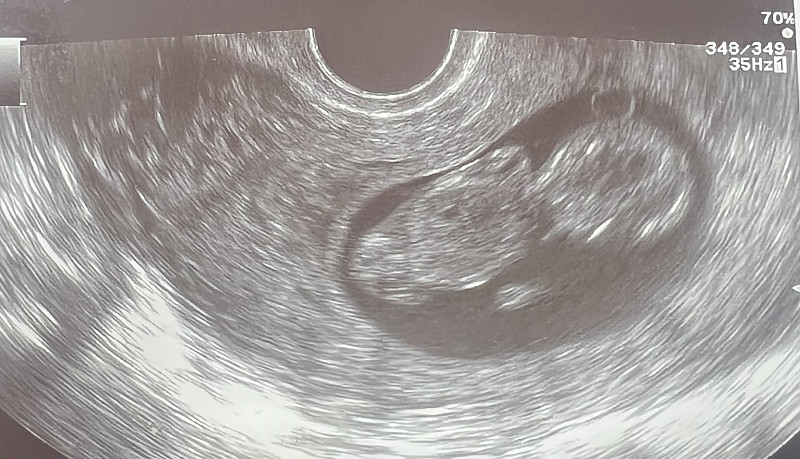

- Nėštumas